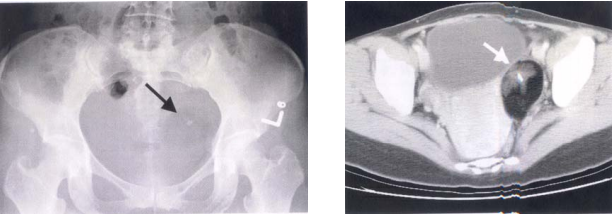

75 40 歲林女士發現數月來月經不規則出血。醫師為她做腹部 X 光攝影,顯示骨盆腔病變如左下圖示。接 著又為她做骨盆腔之 CT 檢查,結果發現異常如右下圖示。林女士最可能罹患什麼病?

(A)子宮內妊娠囊(intrauterine gestational sac) (B)異位性妊娠(ectopic pregnancy) (C)卵巢皮樣囊腫(dermoid cyst) (D)卵巢癌(ovarian cancer)